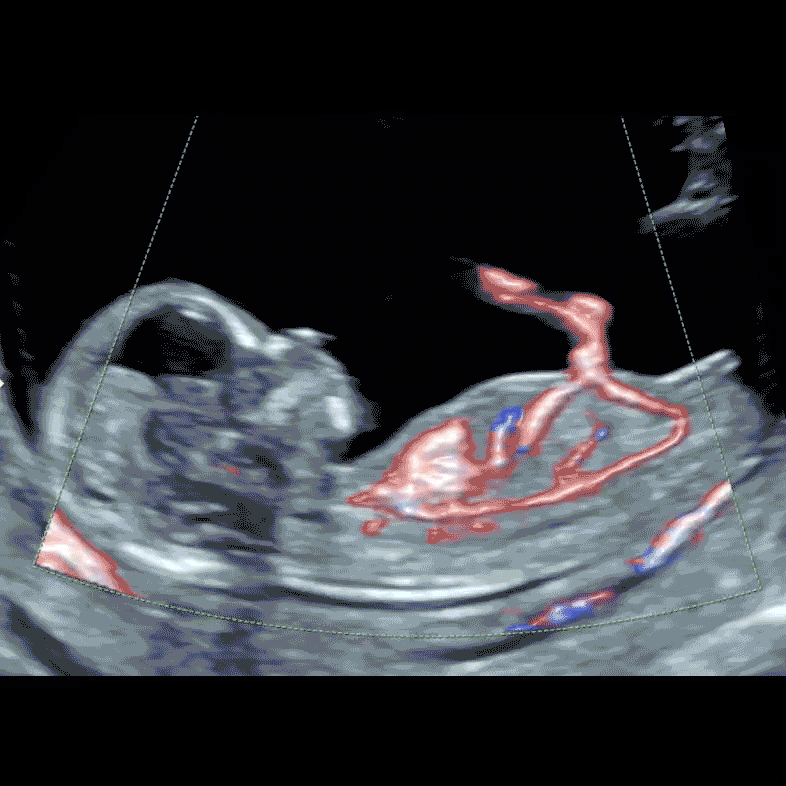

Baby’s heart, main arterial and venous vessels and umbilical cord blood flow by our special colour Doppler technology at 12 weeks

With the Early Fetal Echocardiography at 12-13 weeks the fetal heart is about the size of corn grain, however with our advanced ultrasound technique we will check position of the heart and stomach, presence and size of all four chambers, presence and size of two great arteries and their positions. We also will check the blood flow inside the heart and on cardiac valves by advanced Colour Doppler technique.